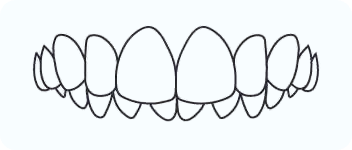

Over Bite

An over bite is when the upper front teeth close down too deeply over the lower front teeth.